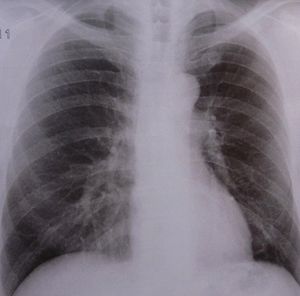

Lunge: Frühere Diagnose bei COPD möglich (Foto: pixelio.de, Dieter Schütz) |